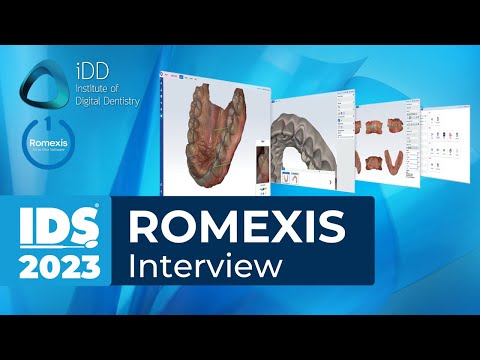

Planmeca Romexis is a robust dental imaging software suite designed to satisfy the evolving needs of dental facilities, from small clinics to large hospitals. Built to support both 2D and 3D imaging modalities, this platform integrates advanced imaging, CAD/CAM, PACS, and analytics under one umbrella, ensuring a seamless and efficient workflow for dental professionals.

- Comprehensive Imaging Modalities: Supports a wide range of 2D and 3D imaging techniques, meeting the varied demands of modern dental practices.

- CAD/CAM Integration: Enabling the design and production of dental restorations through integrated computer-aided tools.

- Seamless Workflow: Consolidates imaging and diagnostic processes into one unified platform, reducing the need for multiple disparate systems.